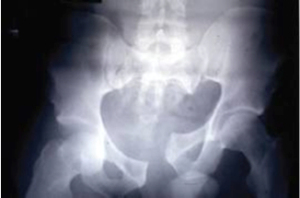

The final group that we have not yet considered in the Young and Burgess classification is the vertical shear group. These patients are complex because the injuries are both horizontally and vertically unstable. You will see what I mean if you have a look at this Xray:

Is putting a binder around the…